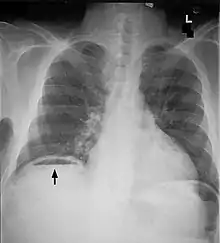

Free air under diaphragm seen on abdominal X-ray.

Abdominal free air

Perforation

Bowel perforation presents with abdominal pain, free air in the abdomen on standing X-ray, and sepsis.[15][16][17] Depending on the cause and size, perforations may be medically or surgically managed. Some common causes of perforation are cancer, diverticulitis, and peptic ulcer disease.